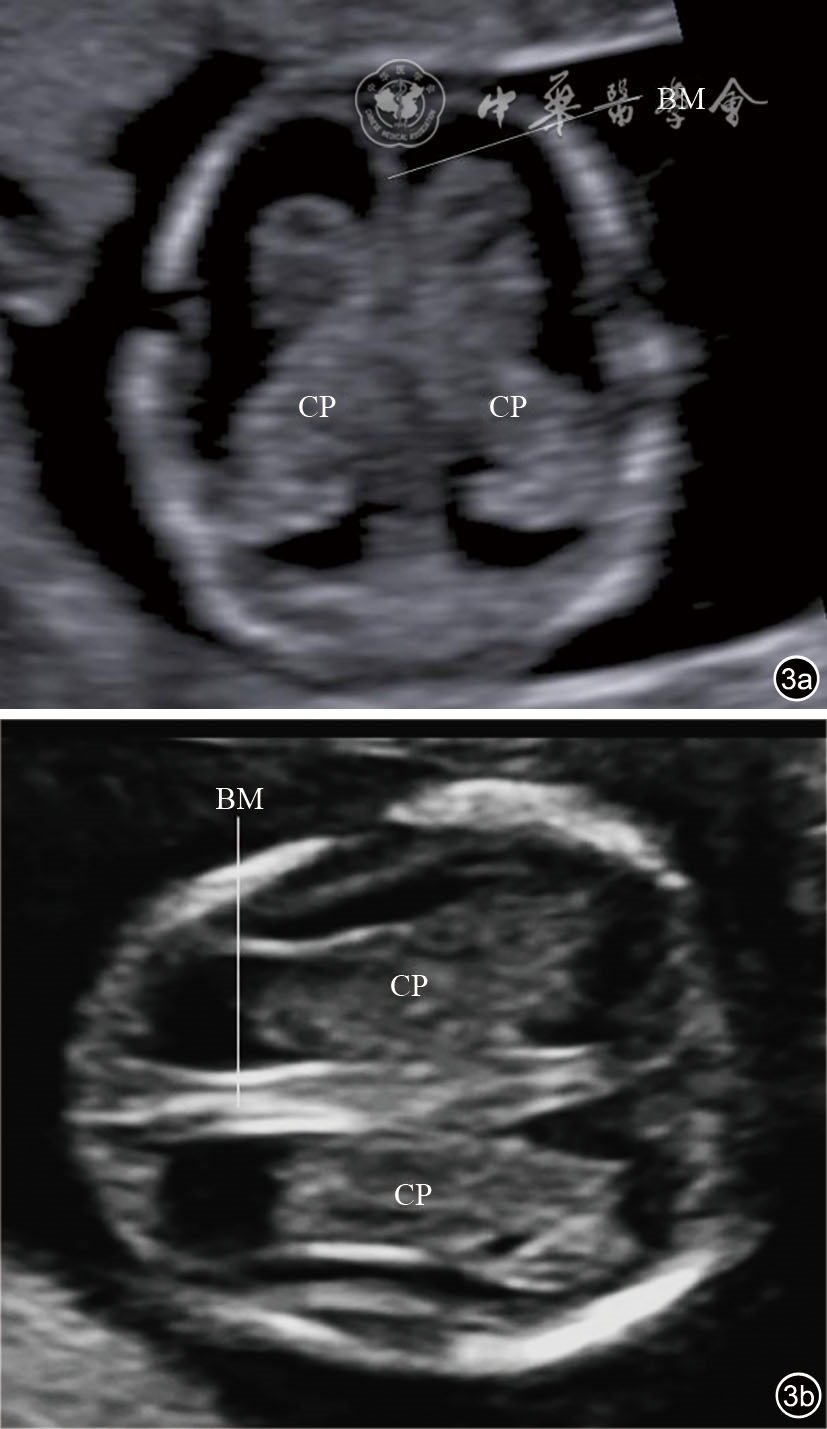

图3 经侧脑室横切面超声图像。图a为妊娠12+4周胎儿经前额侧脑室横切面声像图;图b为妊娠13+3周胎儿经颞部侧脑室横切面声像图 注:CP为脉络丛;BM为脑中线